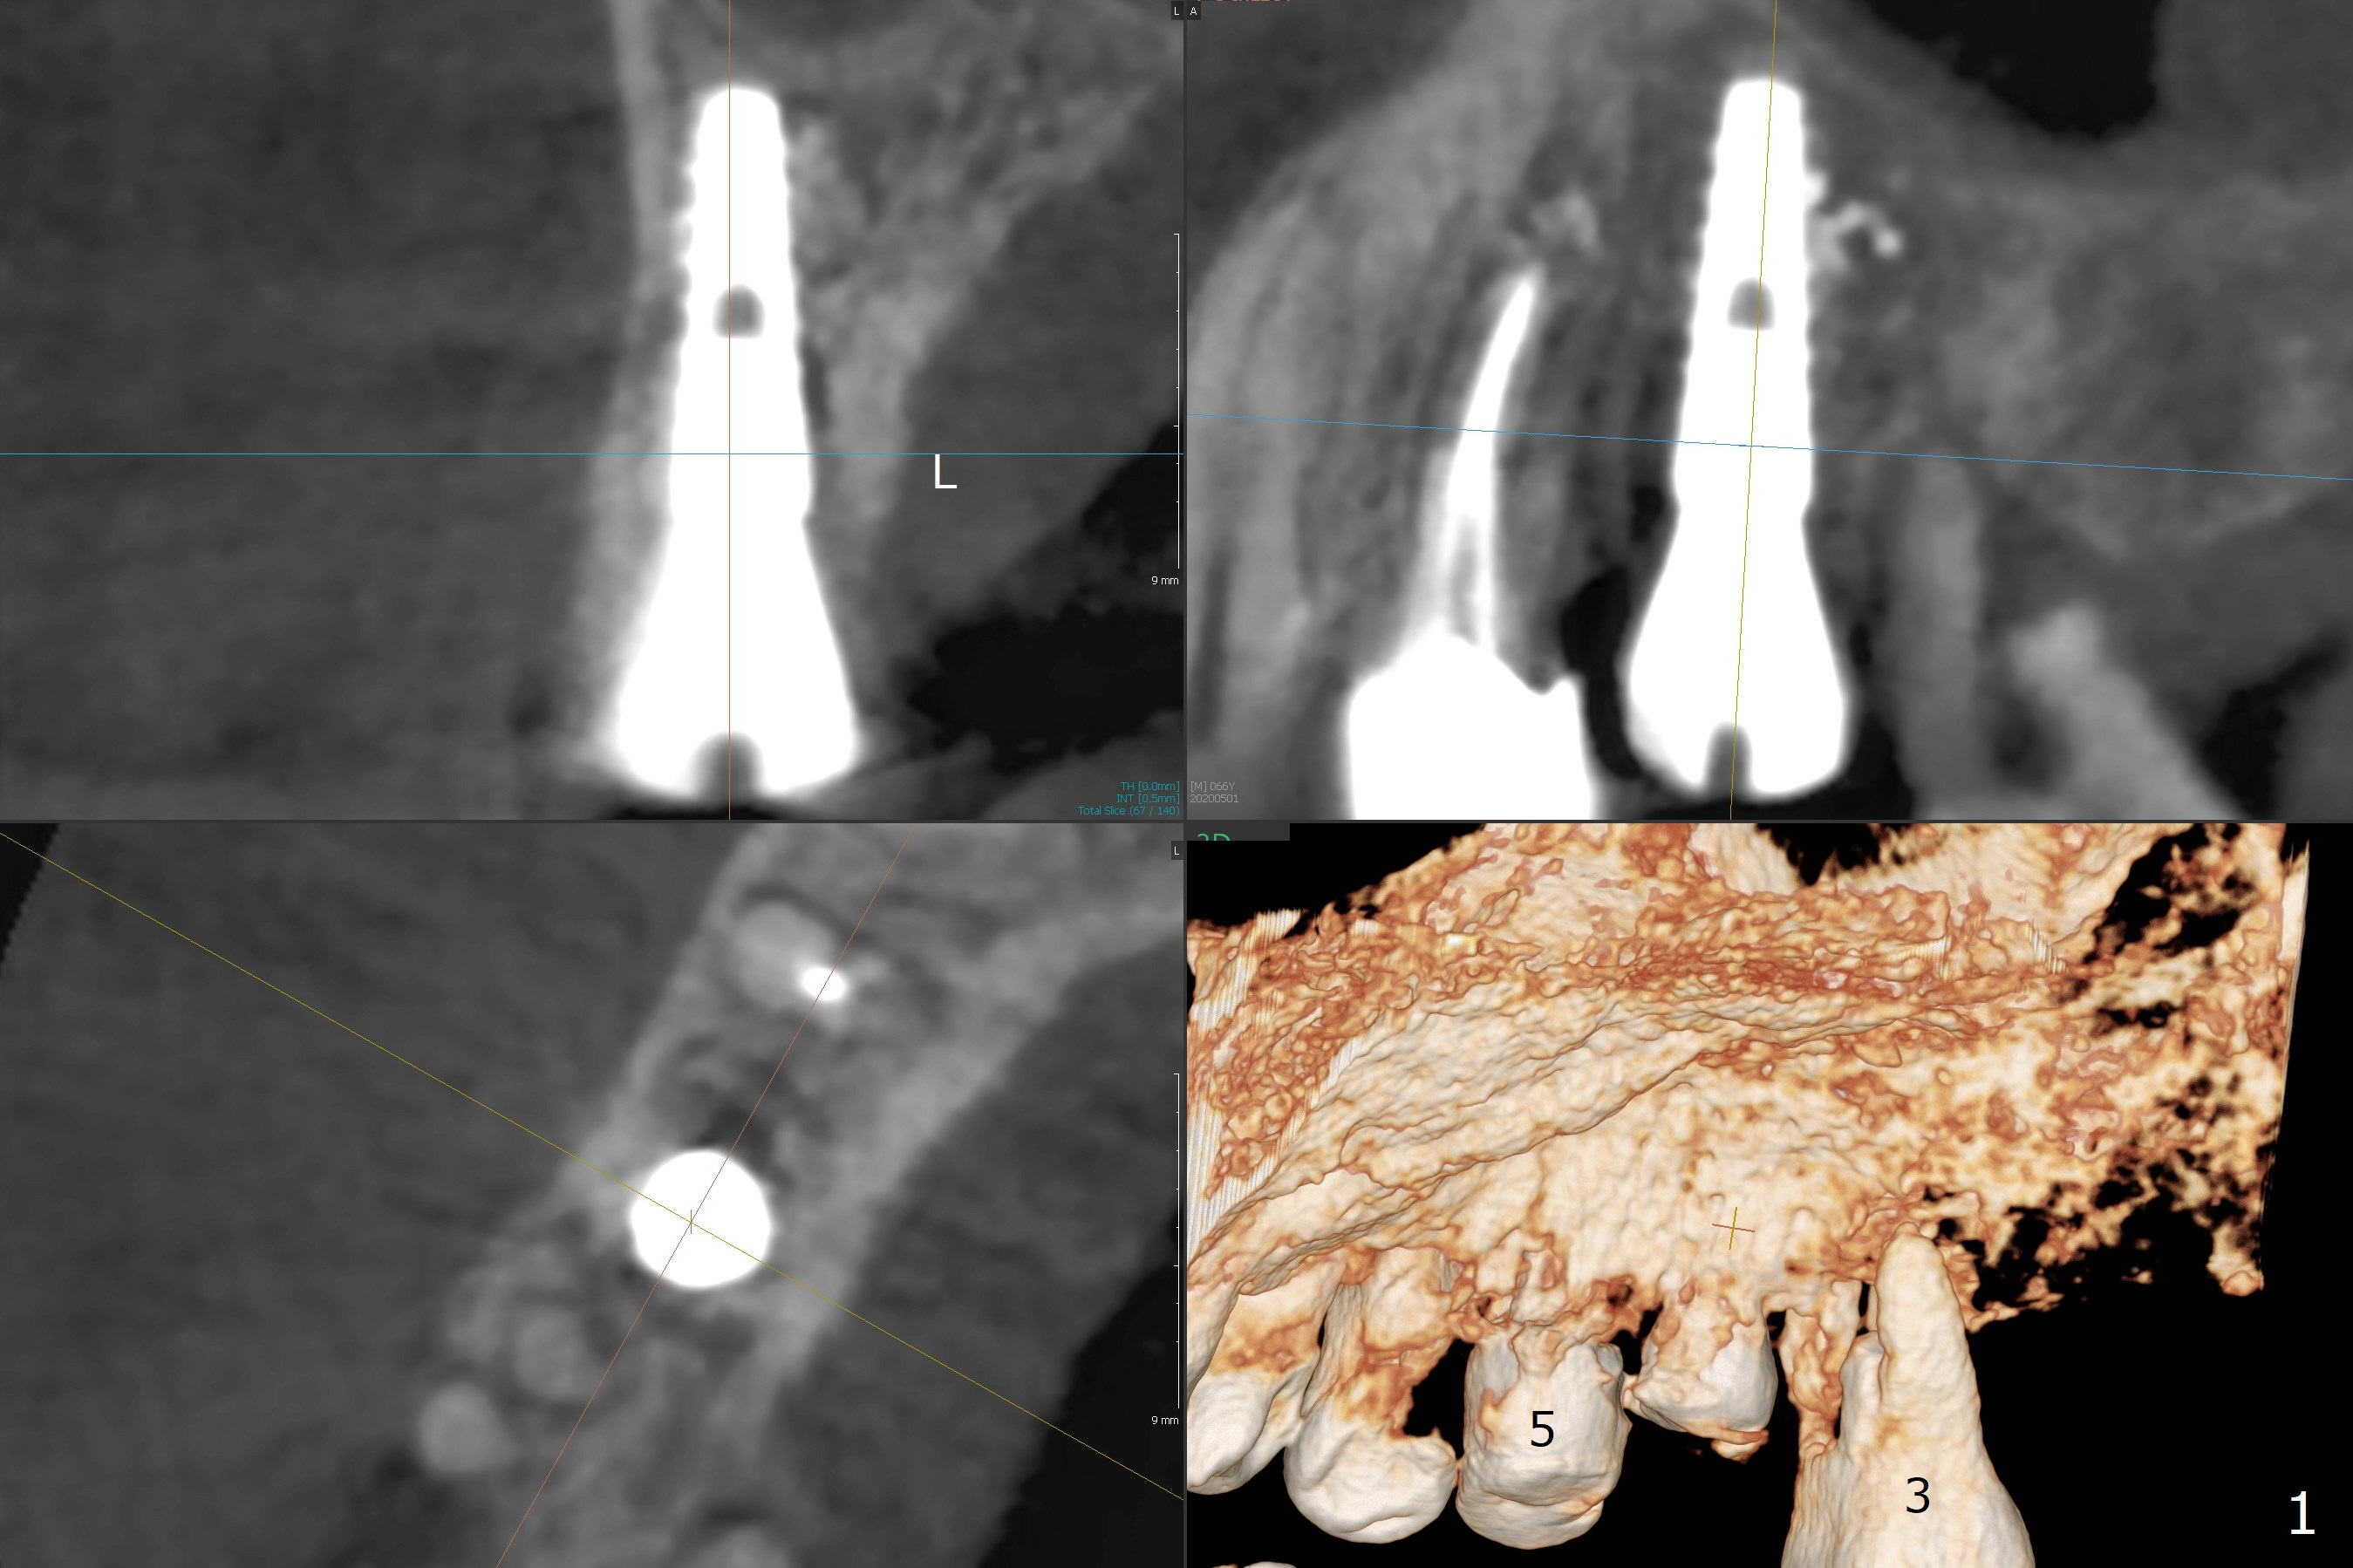

The patient returns for #4 extraction and immediate implant the 1st day clinic reopening after coronavirus lockdown. To reuse autogenous bone for #4 buccal gap closure, delayed implants are also placed at #13 and 14. It is much easier to determine the placement level of the immediate implant (open socket) with guide than that of the delayed ones (flapless) clinically. Immediate postop CT is taken for implant placement level confirmation (Fig.1-3). In fact the autogneous bone is too soft to be packed into #4 socket gaps. It has to be mixed with allograft to be packable. There is oozing when #14 healing abutment is placed. The hemorrhage is severe 4 days postop. The healing abutment is replaced by a healing screw. Hemostasis is achieved when the access is closed with GEM Cap and 4-0 Chromic gut suture. The patient will return for #3 extraction and socket preservation 1 month postop (Fig.4). To prevent postop hemorrhage, a cemented or temporary abutment will be placed at #4 before anesthesia, while .5 or 1.0 cc Augma bone will be placed at #3, covered with collagen plug and acrylic. In fact he cancels the appointment once because of symptom relief and will return 2 months postop. Sticky bone (Fig.5 *) and PRF is used at #3 for hemostasis, while a 5x5.7(3) mm pair (final) abutment is used to hold acrylic dressing in place. The latter remains in place with good oral hygiene 1 month postop (Fig.6 A: abutment). When the acrylic dressing is removed, the socket heals (Fig.7 K: the gingiva between the buccal and palatal sockets when the tooth was removed). The patient returns for impression 4.5 months postop. When the 5x5.7(3) mm abutment at #4 is reseated after cleaning, there is no horizontal gap between the abutment and implant in BW (Fig.8), while there is in PA (Fig.9). When a smaller abutment is seated (Fig.10), there appears to be a horizontal gap, whereas there is no vertical one. The situation is the same with #13 (Fig.11,12). The common denominator is 3.5 mm implant. With suspicion, BW is taken for the implant at #4 immediately before cementation (Fig.13). It appears that the abutment is most likely seated completely. There is no bone loss or screw loosening 4 months post cementation (Fig.14,15). One month later the patient agrees to have 3 lower implants to replace RPD.